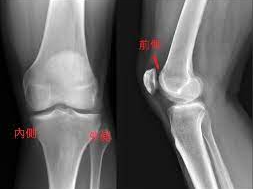

무릎 인공관절 수술이 필요한 이유

나이가 들면 관절 사이 연골이 점차 닳아 없어지면서 뼈와 뼈가 직접 맞닿아 통증을 유발합니다. 특히 무릎은 체중을 지탱하는 관절로써 손상되기 쉬우며, 다음과 같은 증상이 있다면 인공관절 수술이 필요할 수 있습니다.

- 지속적인 무릎 통증으로 일상생활이 어려운 경우

- 계단 오르내리기나 걷기조차 힘든 경우

- 약물치료, 주사치료, 물리치료 등의 보존적 치료에 반응이 없는 경우

- 관절 변형이 심하게 진행된 상태

이런 경우에는 무릎 인공관절 치환술이 가장 효과적인 치료법으로 여겨지며, 수술 후에는 통증 완화 및 활동 능력 회복이 가능합니다.